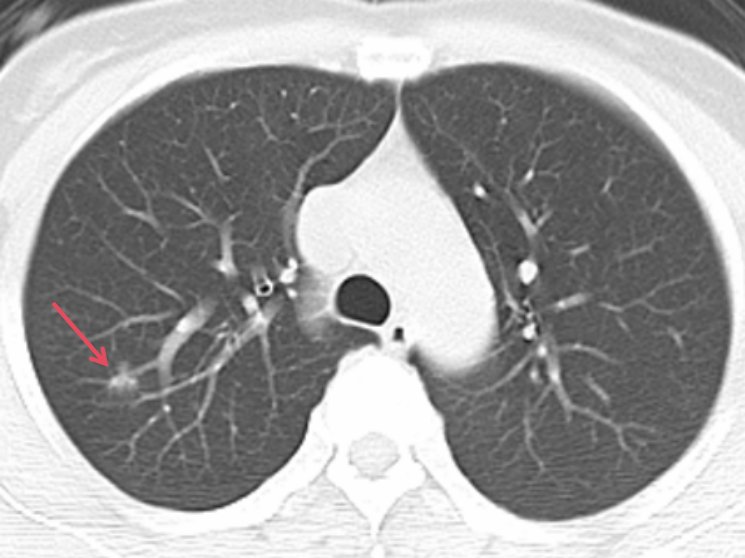

商报全媒体讯(椰网/海拔新闻记者 孙鑫 通讯员 杨树博 赵宏光)随着胸部CT筛查的广泛应用,越来越多的肺磨玻璃样结节被发现。49岁的患者李女士在去年的一次常规体检中,胸部CT扫描发现她的右肺上叶有一个约11mm×10mm的小结节,且该结节呈磨玻璃样改变。医生告诉她,这可能是肺癌的早期迹象——具有生长缓慢,浸润不强,不发生转移,切除后也不会复发等特点。这个消息像晴天霹雳,让李女士陷入了恐慌。

对李女士的病情,赵宏光主任团队高度重视,在吴毓优主任医师、刘运仲副主任医师的配合下,赵宏光主任精准阅片,分析肺段结构后,决定为其行胸腔镜下右上肺后段切除术。

为什么李女士的肺结节要做肺段切除呢?赵宏光主任介绍说,李女士的肺结节远离肺表面,手术中难以触及,无法行肺楔形切除术,只能行肺段切除术。肺段手术技术要求高,不但需要术前对肺结节进行精准的肺段定位和手术规划,还要求术者具有极强的解剖知识、手术技能和处理手术意外情况的经验,术中也要精细、精准。无论哪一环节出现问题,手术都难以进行。

术前,赵主任团队分析肺段动脉、静脉及支气管,并准确定位结节位置,精准分析切除范围,制定肺段切除计划。术中,由于李女士叶间裂发育不全,给后段切除手术造成了一定阻碍,但赵宏光主任凭借着坚实的解剖知识及高超的手术技巧和丰富的手术经验,清晰地将各个结构分离并离断各支肺段动脉、静脉及支气管,精准地切除右上肺后段。